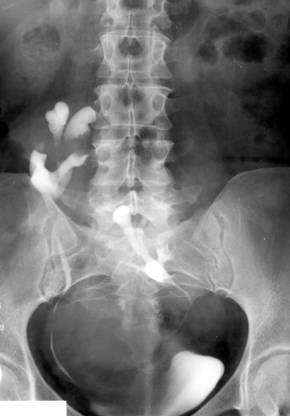

Fig. 60 – Rinichi in potcoava

c. Rinichiul in potcoava – reprezinta fuziunea rinichilor la nivelul polilor superiori sau inferiori printr-o bridă 636i89g ; de tesut renal dispusa in fata aortei, coloanei si venei cave inferioare.